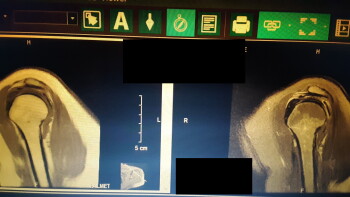

L'effet indésirable dans le bras nécessite maintenant une intervention chirurgicale. Orthro chirurgien, IRM confirment que les dommages proviennent de la réaction et non du placement de l'aiguille. En outre, la fatigue extrême, avait des tremblements et du brouillard cérébral.